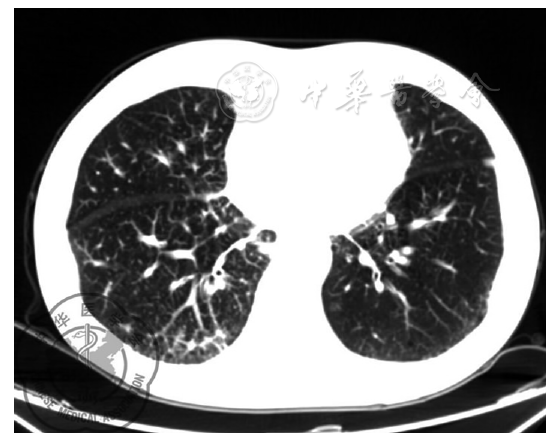

图1 A、B:2015年9月,在我市某三甲医院门诊胸部CT,提示:双肺间质性改变,纵隔多发淋巴结肿大;2、双肺气肿,多发肺大泡;C、D:2015年12月,另一医院门诊胸部CT,提示:双肺间质性改变,伴右侧肺门结构不清,纵隔多发淋巴结肿大,肿瘤病变伴癌性淋巴管炎?间质性炎症待排;双肺气肿,多发肺大泡;心包积液

图3 胸部CT检查:右下肺癌治疗后复查,心包、胸腔未见明显胸腔积液